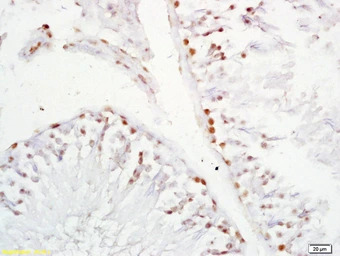

IHC-P analysis of rat testis tissue using GTX51780 XAGE2 antibody.

Dilution : 1:200